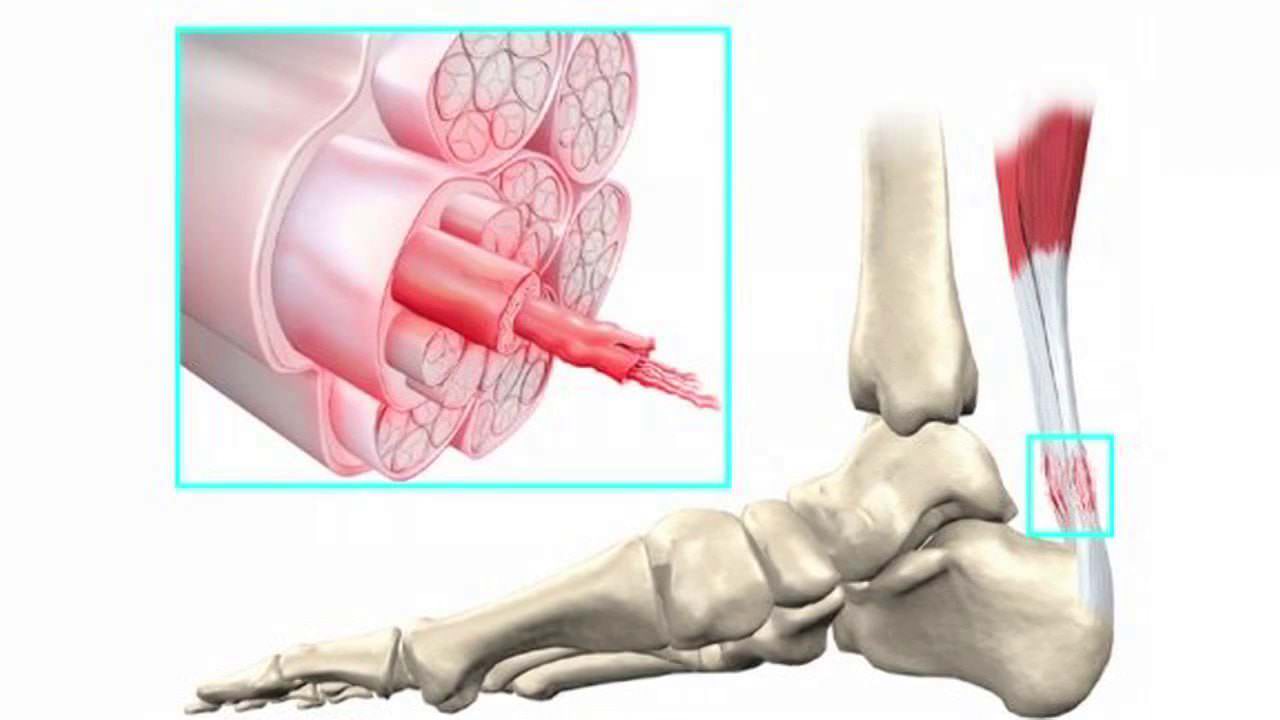

גורם #2: דלקת גיד אכילס

גיד האכילס הוא הגיד העבה ביותר בגוף והוא חשוף ללחץ יומיומי.

בנוסף לכאב והנוקשות, גיד האכילס יכול לגרום לנפיחות בקרסוליים ועקבים. הנפיחות יכולה להחמיר אחרי פעילות פיזית.